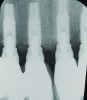

Fig 1 through Fig 6. Periapical radiographs of a 52-year-old man who received a fixed porcelain-fused-to-metal reconstruction supported by abutments attached to externally hexed dental implants. Fig 1 through Fig 3 are at initial prosthesis placement: maxillary right (Fig 1), textured surfaced threaded titanium implants at site Nos. 2, 4, and 6; maxillary anterior (Fig 2), implants at site Nos. 7 through 9; maxillary left (Fig 3), implants at site Nos. 12 and 14. Fig 4 through Fig 6 are 10 years post-insertion of the prosthesis: maxillary right (Fig 4), maxillary anterior (Fig 5), and maxillary left (Fig 6). Note minimal to no bone loss radiographically around the implants 10 years post-insertion of prosthesis.

Fig 7 through Fig 14. Periapical radiographs of a 62-year-old woman who received a fixed porcelain-fused-to-metal reconstruction supported by abutments by internally connected dental implants. Fig 7 through Fig 10 are at initial prosthesis placement: mandibular site Nos. 30 and 29 (Fig 7); mandibular site Nos. 26, 25, and 23 (Fig 8); mandibular site Nos. 23 and 21 (Fig 9); mandibular site Nos. 21 through 19 (Fig 10). Fig 11 through Fig 14 are 11 years later (2013) and show excellent preservation of the vertical bone levels around the implants: mandibular site Nos. 30 and 29 (Fig 11); mandibular site Nos. 26 and 25 (Fig 12); mandibular site Nos. 25 and 23 (Fig 13); mandibular site Nos. 20 and 19 (Fig 14). It is interesting to note that in the mandibular right posterior quadrant there is a matched pair, ie, an external hex dental implant (No. 30) adjacent to an internally connected dental implant (No. 29). The bone levels around each of these designs are well-preserved at the 11-year follow-up.

During the first year after implantation, patients with completely restored edentulous ridges demonstrated a mean total bone loss ranging from 0.90 mm to 1.64 mm.58-60 After the first year, the mean annual rate of bone resorption ranged from 0 mm to 0.15 mm58-65 (Figure 1 through Figure 14).